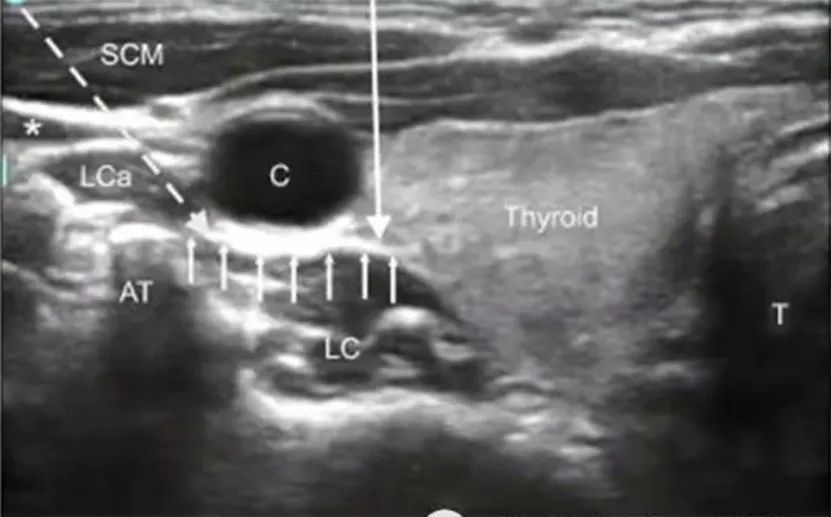

星状神经节位于第七颈椎横突处,椎前筋膜的深面,与椎动脉起始部、膈神经干、肺尖、胸膜顶、胸导管相邻,此处解剖位置复杂, 单任经验和感觉很难精准操作。在超声引导下,星状神经节清晰可辨,阻滞术可精确穿刺至颈部星状神经节周围,同时避免损伤周围重要组织,安全、微创、痛苦小、无辐射。给药全程超声可视,可谓是“看得见”的治疗,大幅降低了传统盲打易出现的血管神经损伤、气胸等发生率。